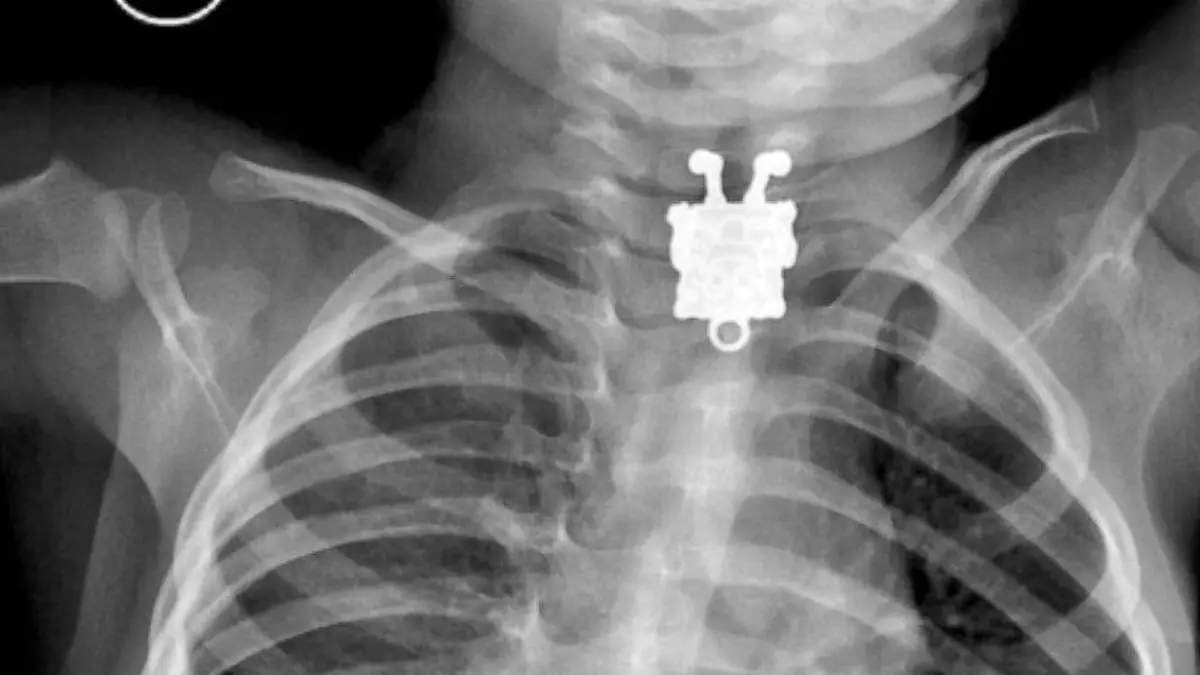

رکنا: پزشکان عربستانی در جراحی موفقیتآمیزی یک سنجاق فلزی را از گلوی نوجوان 16 سالهای بیرون کشیدند.

به گفته پزشکان این سنجاق فلزی با قالب «باب اسفنجی» شخصیت کارتونی محبوب کودکان و نوجوانان تزیین شده بود. پزشک جراح این نوجوان میگوید: «من ابتدا با دیدن تصاویر رادیولوژی از این شخصیت مکعبی کارتونی تعجب کردم اما وقتی شکم این نوجوان شکافته شد باب اسفنجی فلزی که سر و ته قرار گرفته بود با لبخندی بزرگ روی لبش ما را شوک زده کرد.»

به گفته پزشکان باتوجه به چرخش این سنجاق در بدن این نوجوان، این سنجاق در میانههای راه شکم گیر کرده و به سیستم گوارشی آسیبی نزده است.